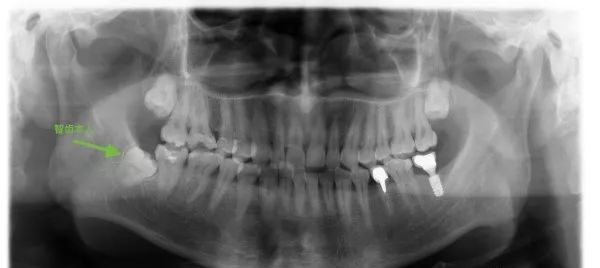

大家要是比對(duì)一下自己的全景 X 片,看著那些還沒(méi)來(lái)得及拔掉的智齒,有沒(méi)有人會(huì)覺(jué)得自己簡(jiǎn)直「負(fù)債上億」!

比如這種:

圖片來(lái)源:作者提供

這可怎么拔出來(lái)?